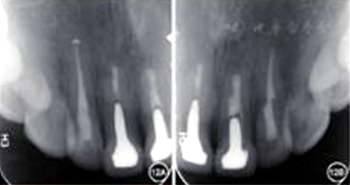

6.再治疗术后2年复查:

见图12,图13。临床检查叩诊正常,不松动,牙龈色泽正常,切口位置可见隐约瘢痕。根尖X线片显示根尖无明显病变。

图12 术后2年复查患者根尖X线片 A:根尖无明显病变;B:根尖无明显病变